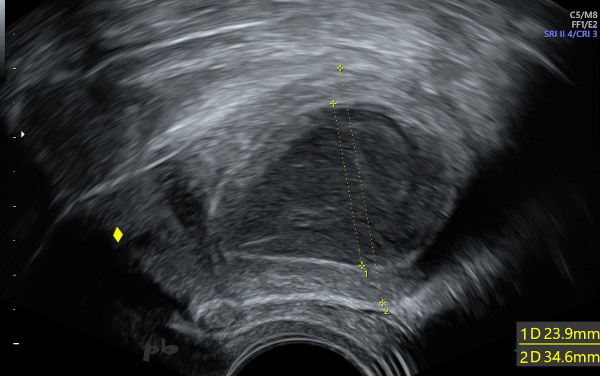

6 – Diagnostic différentiel : pyométrie

Echographie endovaginale.

Métrorragies post-ménopausiques.

Dilatation de la cavité utérine (croix 1) par un liquide hypoéchogène hétérogène.

Le curetage révèlera qu’il s’agissait de pus.

Emdométrite à l’anapath.

Col utérin (♦)